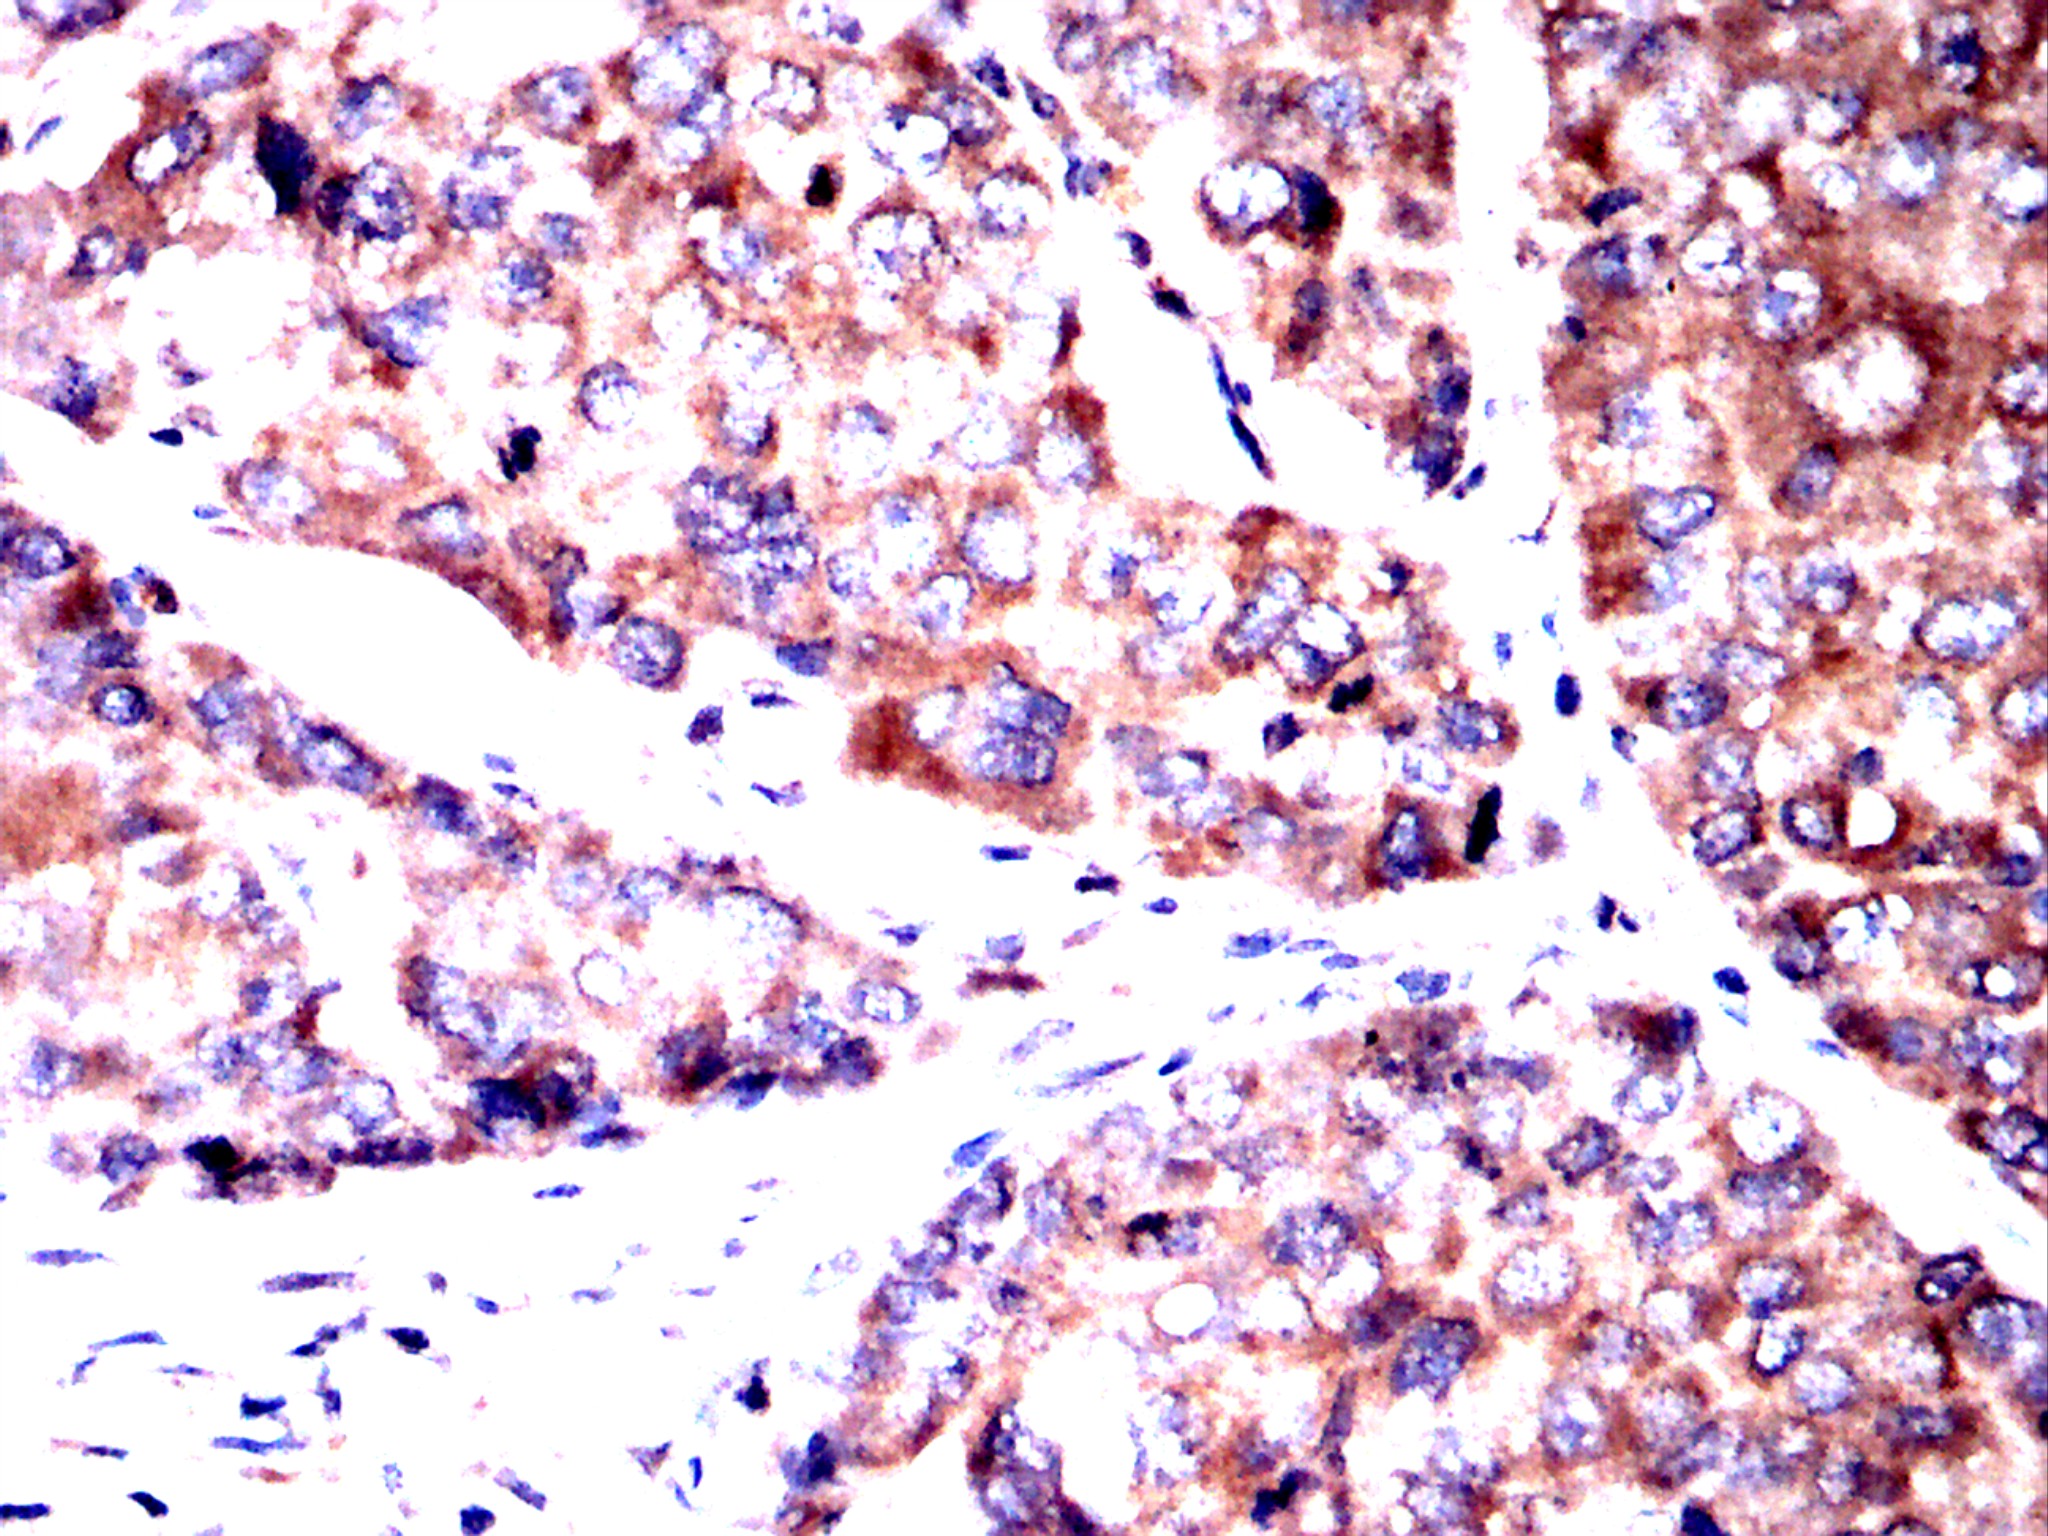

Immunohistochemical analysis of paraffin-embedded breast cancer tissues using PSMB8 antibody with DAB staining. Pre-treat the sections with heat-mediated antigen retrieval using sodium citrate buffer (pH 6.0) (OM750020) for 2 minutes. Wash the sections with ddH₂O and PBS (OM750003). Block the tissue with 10% non-immune goat serum(OM760028) at room temperature for 30 minutes. Incubate the tissue with the primary antibody diluted at a ratio of 1:1500 at 4°C overnight. At room temperature, dilute the secondary antibody, Goat Anti-Rabbit IgG(H&L)-HRP (OM643487), at a ratio of 1:200 and incubate for one hour. Use DAB(OM760029)as the chromogenic agent. Counterstain the tissue with hematoxylin, and mount the tissue sections with neutral gum.WB

Immunohistochemical analysis of paraffin-embedded breast cancer tissues using PSMB8 antibody with DAB staining. Pre-treat the sections with heat-mediated antigen retrieval using sodium citrate buffer (pH 6.0) (OM750020) for 2 minutes. Wash the sections with ddH₂O and PBS (OM750003). Block the tissue with 10% non-immune goat serum(OM760028) at room temperature for 30 minutes. Incubate the tissue with the primary antibody diluted at a ratio of 1:1500 at 4°C overnight. At room temperature, dilute the secondary antibody, Goat Anti-Rabbit IgG(H&L)-HRP (OM643487), at a ratio of 1:200 and incubate for one hour. Use DAB(OM760029)as the chromogenic agent. Counterstain the tissue with hematoxylin, and mount the tissue sections with neutral gum.